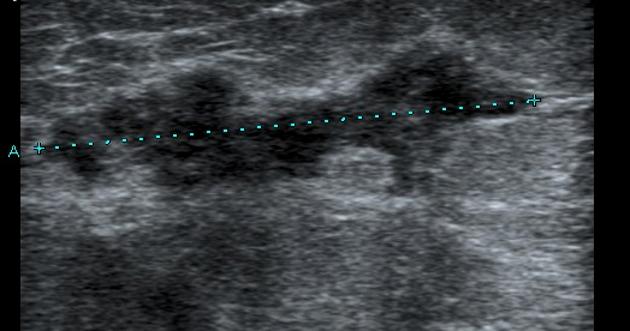

CASE REPORT Idiopathic Granulomatous mastitis

Ultrasound image of the breast. Fig. 3. Histological stain from the core biopsy. Grace Rubin, MB BCh, DA (SA), FCRad (D) SA Idiopathic granulomatous mastitis (IGM) is a granulomatous inflammation of the breast lobules of unknown aetiology. ... Access Document